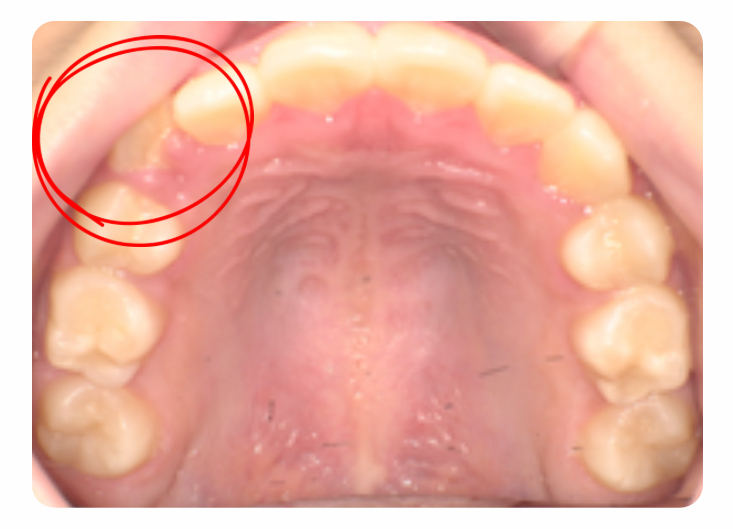

八重歯になるかどうか・・・

アクティビティは約2〜3年で終了するプログラムです。

そのためアクティビティ終了時にはまだ9歳で、乳歯が多く残っていました。

そのため全ての歯が生えるまでは経過を見ていましたが

前から3番目の歯(犬歯)が生え変わる際にスペースの不足が認められました。

この歯は乳歯から永久歯に変わる時1.5〜2倍ほどの大きい歯に変わるのでこのままでは

八重歯になることが予測されました。

補助装置(BWS)の使用

生え変わるタイミングでBWSという補助装置を使用し、上顎の骨をより前方に成長させました。